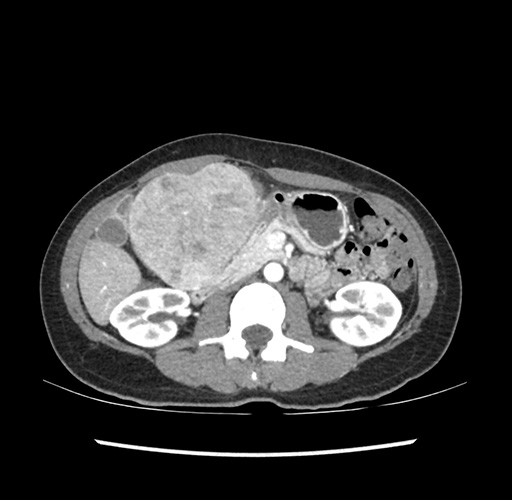

Imaging Analysis

Look through the patient's CT scan to identify any areas of concern for the necessary procedure.

Based on your CT findings, which issue(s) would give reason for "planned slowing down moment(s)" in this case?